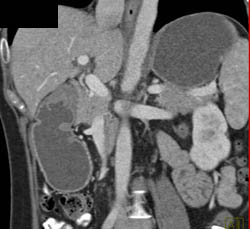

Antral Carcinoma